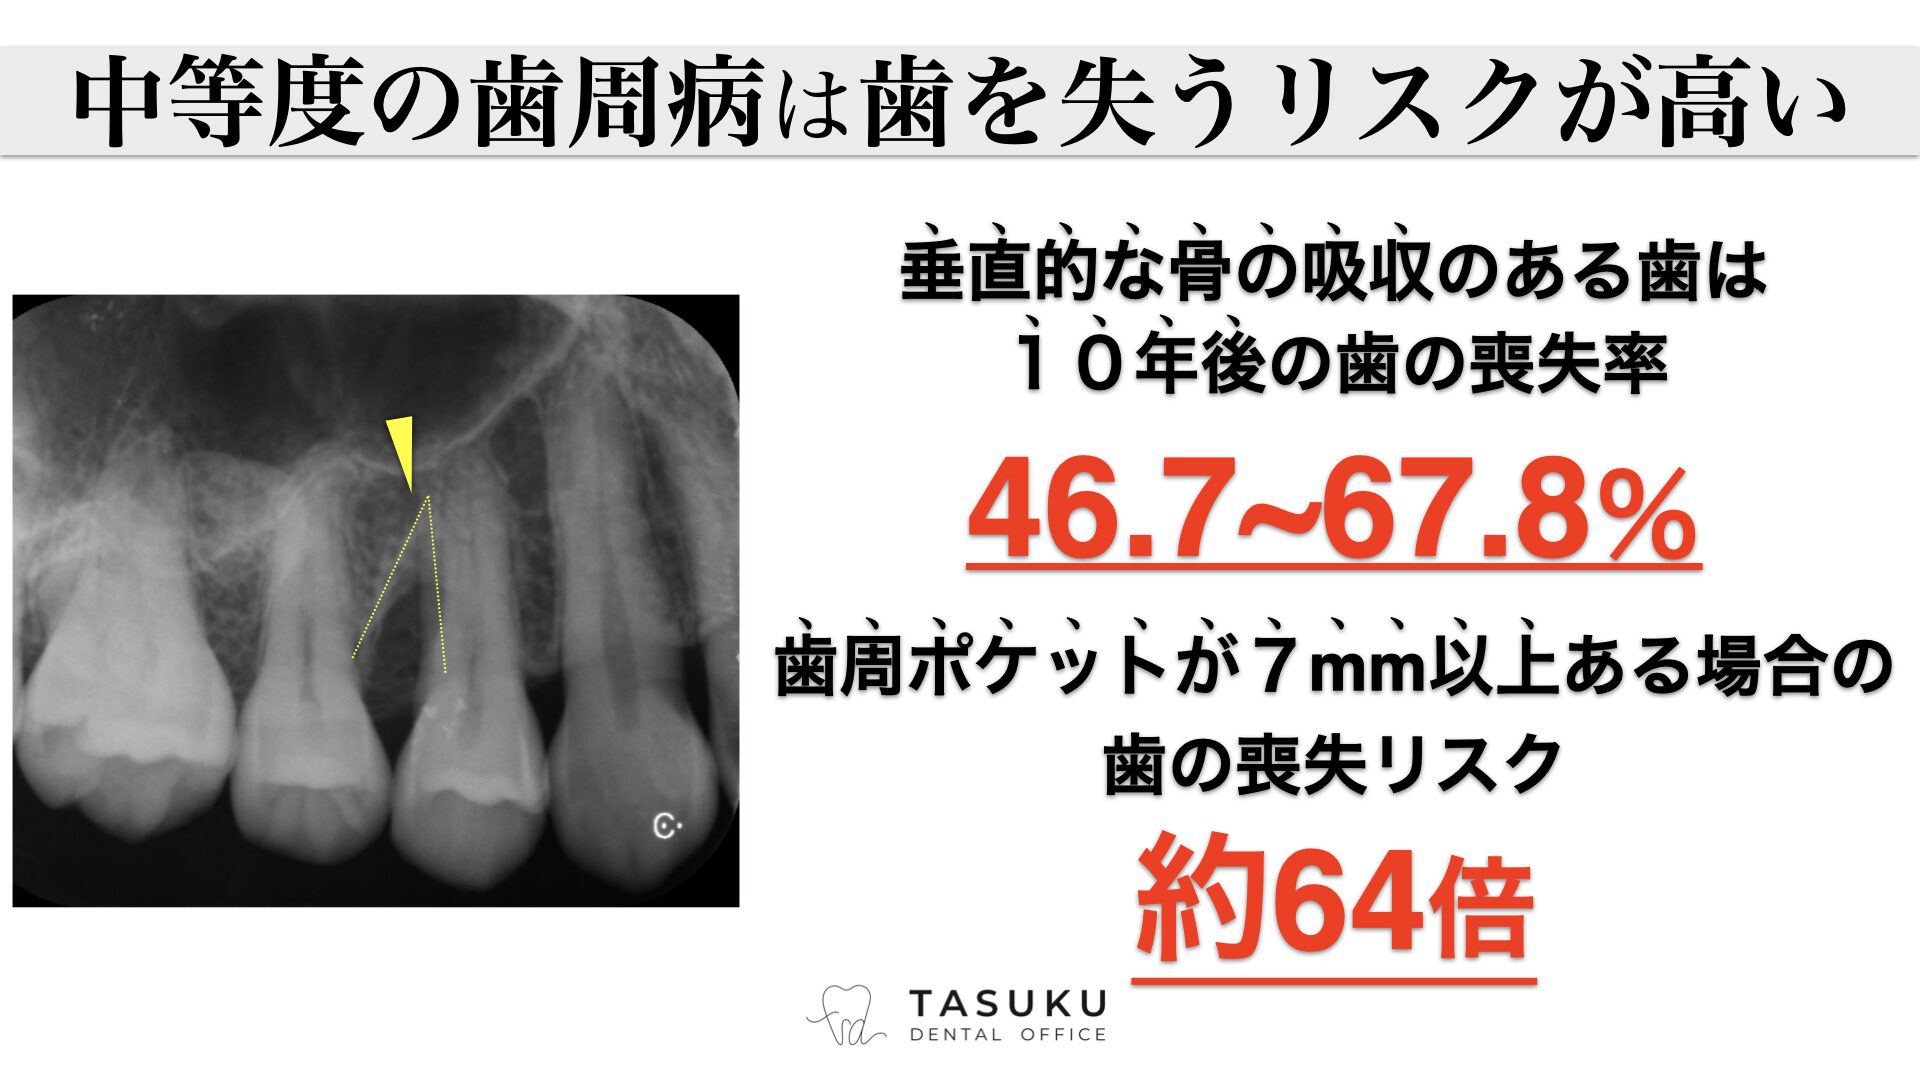

歯周外科治療Periodontal surgery

基本的な歯周病治療のほか、歯周組織を再生する治療や、歯肉の移植なども行います。認知症をはじめとする、全身疾患の要因にもなる歯周病を原因から改善します。